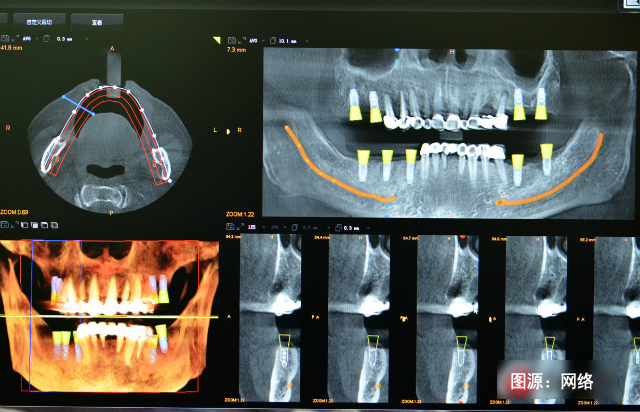

受植區(qū)良好的骨條件是實(shí)現(xiàn)植體與骨整合的重要因素,為了預(yù)防及減少牙槽嵴的廢用性萎縮和吸收,使牙槽嵴骨量的高度、寬度及密度滿足后期種植的需要,需在拔牙后種植前對其位點(diǎn)進(jìn)行保存,即拔牙后軟硬組織量的保存。

3、即刻種植:拔牙后即刻植入種植體是預(yù)防牙槽嵴萎縮的一個(gè)有效方法,它能夠很好地保持牙槽嵴的高度和寬度。